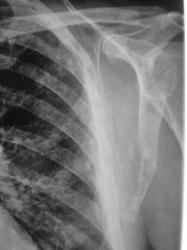

Иллюстрации 3. 4. Слева в области латерального латерального края лопатки, в ребрах определяются участки остеопоротической перестройки структуры костной ткани — литический вариант.